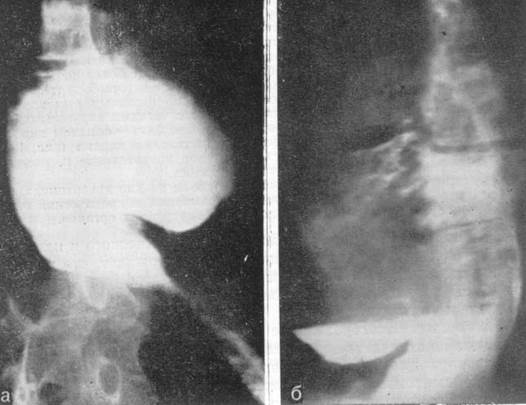

Основной метод выявления эпифренальных дивертикулов - контрастное рентгенологическое исследование (рис. 7) и эзофагоскопия.

Рис. 7. Рентгенограмма. Приобретенный эпифренальный дивертикул и симптоматическая ахалазия кардии. А – передняя; б – боковая проекция.

При больших размерах эпифренального дивертикула, когда клиника сопровождается синдромом сдавления или при дивертикулите показано оперативное лечение - иссечение дивертикула (рис. 8).